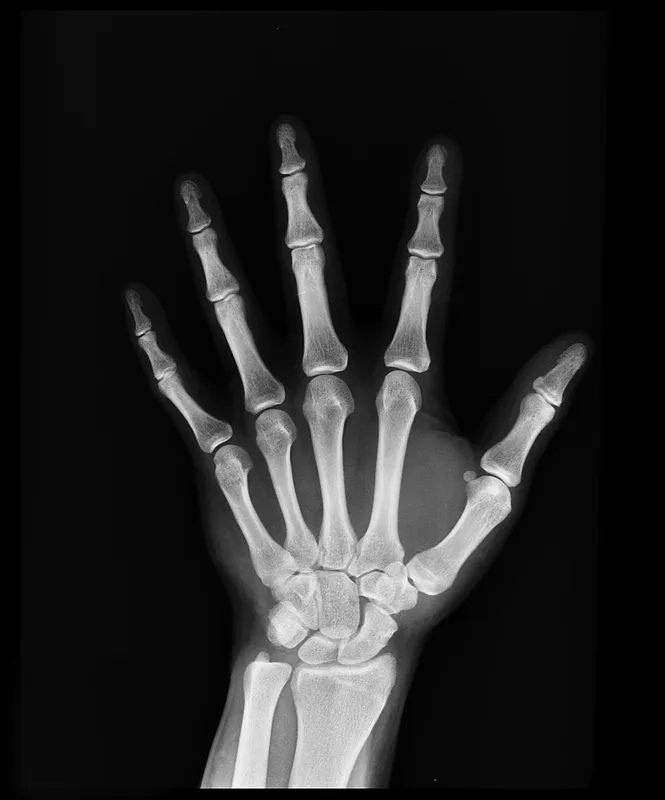

Padlódeszkák darabolása közben, egy elektromos fűrésszel majdnem teljesen kettévágta a bal kézfejét az angol Anthony Lelliott. A 46 éves asztalos egyetlen rossz mozdulattal duplán amputálta magát: levágta a középső ujját, illetve a kézfeje egy darabjával egyben a mutató és a hüvelykujját. A londoni Tootingban működő St. George’s kórház orvosai először sokkot kaptak, amikor meglátták, majd nekiálltak a műtétnek és a csodával határos módon meg tudták menteni a kezét – írja a Sky News.

Lelliott első körben egy tizenhét órás operáción esett át. Az orvosok először helyre tették a törött csontokat, aztán idegeket és érdarabokat műtöttek ki az alkarjából és a lábfejéből, hogy áthidalhassák a csonkolt kézből hiányzó részeket. Az operáció közben az orvosok észrevették, hogy a középső ujjal komolyabb gondok vannak, mint gondolták, ezért úgy döntöttek, azt a testrészt feláldozzák és kéz többi részének megmentésére fókuszáltak. A középső ujj csontjait és bőrét a tenyér rekonstrukciójánál használták fel.

Így sem volt azonban elég bőr a roncsolt kézfejen. Az orvosok kivágtak egy darabot Lelliott bőréből az ágyékánál, majd odavarrták a sérült kézfejet. Két héttel később, amikor az ágyékról elég bőr nőtt át a kézre, a végtagot leválasztották. A plasztikai sebész, Roger Adlard azt nyilatkozta, ez volt a legkomplikáltabb amputációs eset, amivel pályafutása során dolga volt.